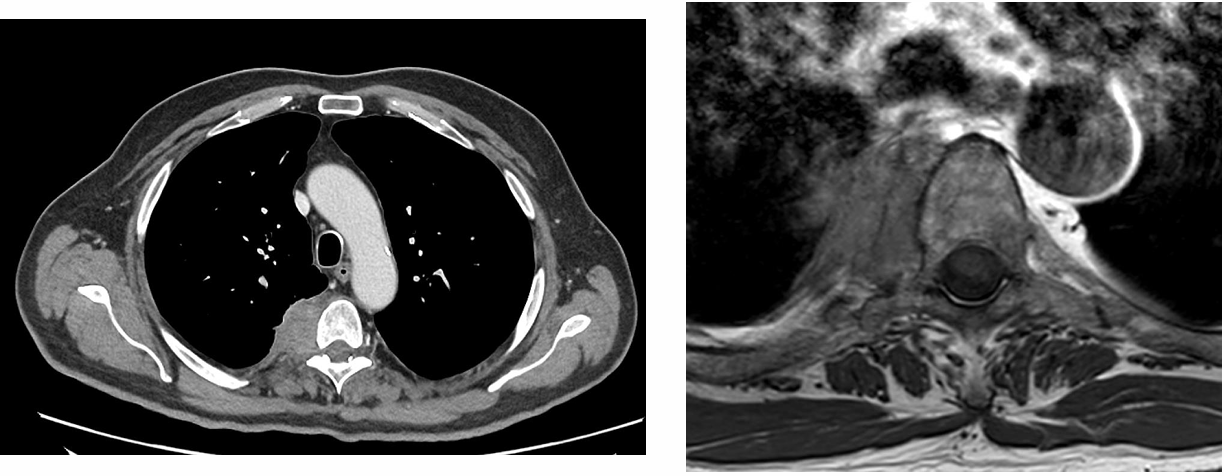

65岁男性,既往重度吸烟史(50包/年),ECOG PS 1分。因肩胛区疼痛入院治疗。胸部CT显示,右肺上叶可见一巨大肿块,最大径达7.3cm。病灶疑似侵犯椎体及胸膜,并伴有可疑的4R组淋巴结肿大。PET/CT显示,原发病灶SUV最高值为17,4R组淋巴结SUV最高值为11。MRI未见转移。临床分期定为cT4N2M0(IIIB期)。